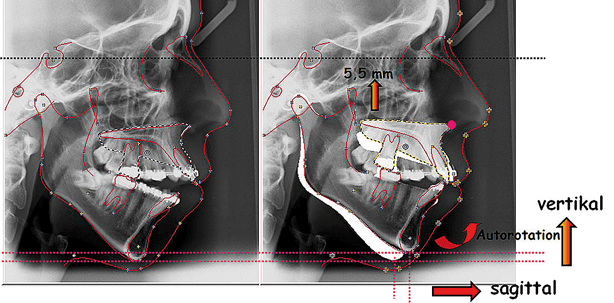

Bei der Kranialverlagerung der Maxilla tritt eine Autorotation des Unterkiefers ein, bei der der Unterkiefer seine Lage in der Sagittalen (ventrale Verlagerung) und in der Vertikalen (kraniale Verlagerung) verändert (Abb. 3). Eine Folge dieser Impaktion und anschließender Unterkieferautorotation ist die Veränderung der anterioren (AFH) und posterioren (PFH) Gesichtshöhe, sodass sich die Relation der posterioren zu der anterioren (PFH/AFH) Gesichtshöhe vergrößert.10,13,31,50 Es tritt eine neue Kieferrelation sowohl in der Vertikalen als auch in der Sagittalen ein. Diese Autorotation ist umso stärker, je größer die Impaktionsstärke der Maxilla ist (Abb. 4), wobei hier das Impaktionszentrum nicht unberücksichtigt bleiben darf. Diese Impaktion abhängig von deren Zentrum führt zu einer Achsenstellung der Frontzähne (Abb. 5). Die Bedeutung und das Ausmaß dieser Bewegungen bzw. Veränderungen können und müssen bei der kephalometrischen Operationsplanung ermittelt und somit berücksichtigt werden.

Neben den oben genannten Behandlungszielen war als besonderes Behandlungsziel die Verbesserung der Gesichtsästhetik nicht nur in der Sagittalen, sondern auch in der Vertikalen zu nennen. Dies sollte durch eine relative Verkürzung des Untergesichtes erfolgen. Eine Verkürzung des Untergesichtes als kausale Therapie mit entsprechendem Effekt auf die faziale Ästhetik und Lippenfunktion konnte bei dieser Patientin nur durch eine kombiniert kieferorthopädisch-Kieferchirurgische Behandlung erreicht werden. Mit alleinigen orthodontischen Maßnahmen wären die angestrebten Ziele hinsichtlich der Funktion und Ästhetik nicht zu erreichen gewesen. Die Dysgnathie war zu gravierend für einen alleinigen dentoalveolären Ausgleich. Als Operation wurde eine Oberkiefer-Osteotomie geplant. Zur Verbesserung der Vertikalen war eine Oberkieferimpaktion notwendig,43,55 die im dorsalen Bereich hauptsächlich durchgeführt werden sollte. Als Folge der Impaktion sollte der Unterkiefer mit den Kondylen als „Rotationszentrum“ in der Sagittalen und Vertikalen autorotieren; dabei war eine Verlagerung des Pogonions (Kinnprominenz) nach ventral und gleichzeitig nach kranial zu erwarten.26,27,31,50 Diese Autorotation des Unterkiefers sollte erwartungsgemäß die sagittale Dysgnathie (distalen Okklusion) korrigieren.

Nach Modelloperation, Festlegung der Verlagerungsstrecke und Herstellung der Splinte wurde am Oberkiefer eine Le Fort-I Osteotomie durchgeführt, bei der die Maxilla im dorsalen Bereich um 5,5 mm und im ventralen Bereich um 1,5 mm nach kranial impaktiert wurde, sodass eine posteriore Rotation der gesamten Maxilla eintrat.43,44,54 Durch die Autorotation des Unterkiefers wurde die Distallage des Unterkiefers korrigiert, sodass eine operative Unterkiefervorverlagerung nicht mehr notwendig war (Abb. 11a–c).17,20,21,32,45,46